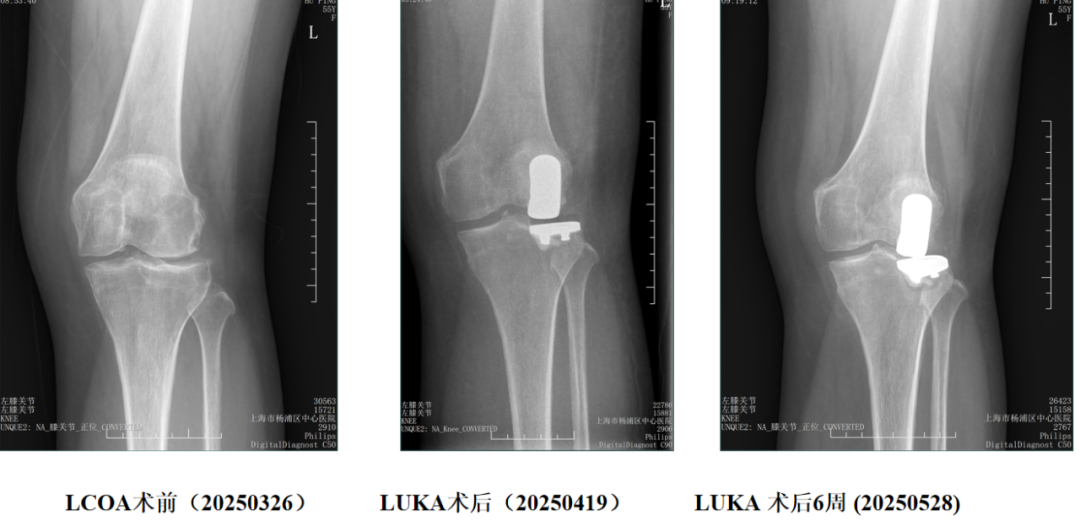

三、胫骨假体下沉翻修

外侧间室OA行LUKA,术后外伤导致胫骨假体塌陷

胫骨假体翻修术(保留股骨假体)

四、胫骨假体过度前倾翻修

LUKA术后胫骨假体过度前倾导致膝关节伸直受限

LUKA术后半年 (20251126)

保留股骨假体胫骨侧翻修

翻修术后 (20251201)